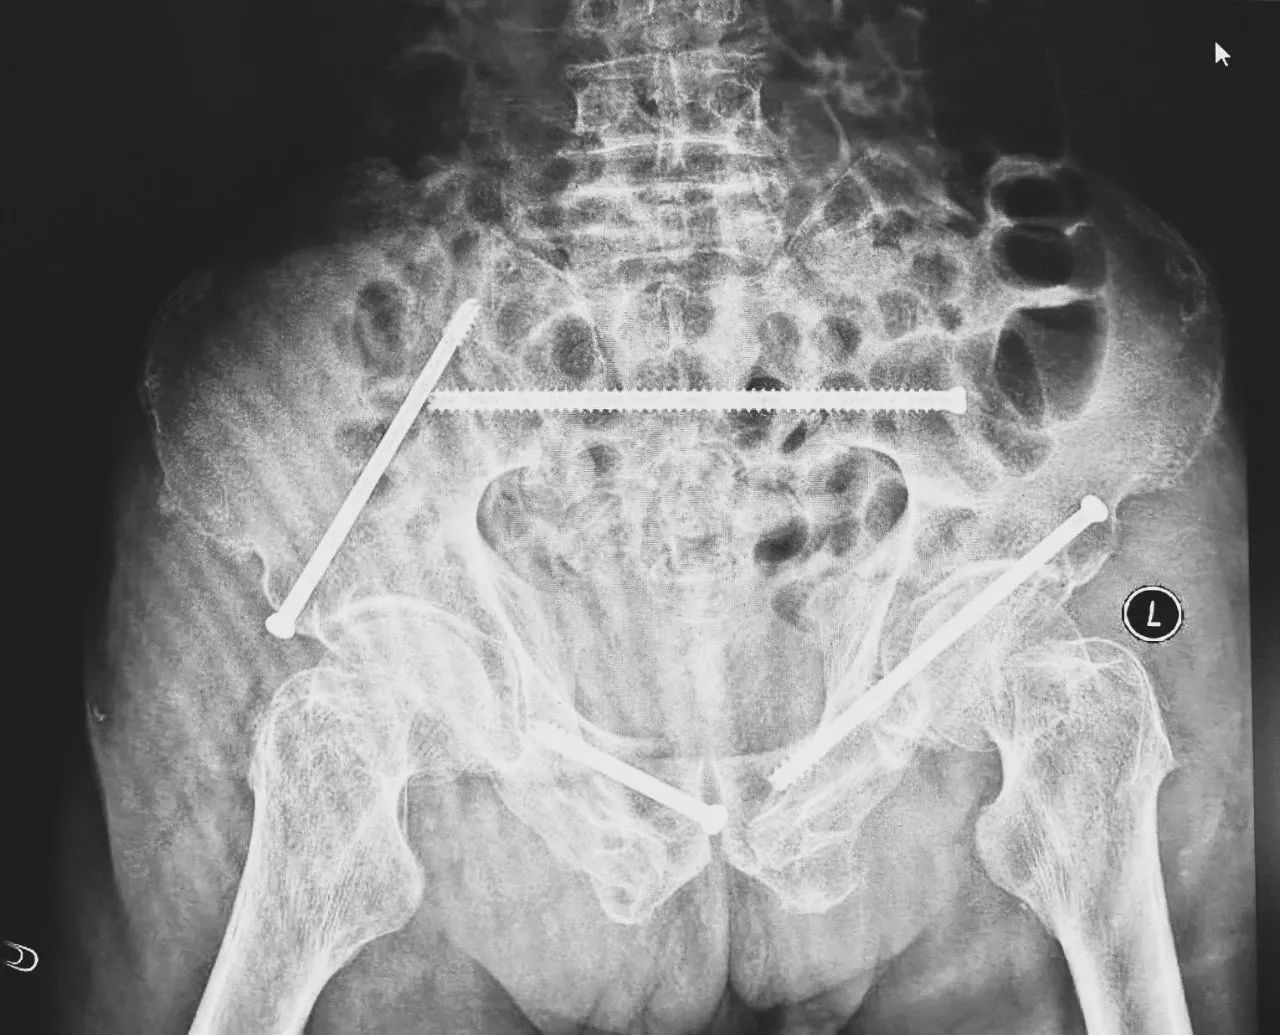

術前影像學顯示,患者的左側骶骨骨折,右側恥骨骨折、髂骨骨折,骨盆骨折分型為C型,老年脆性骨盆骨折分型為IV型,是極度不穩定型的前環骨折和雙側后環骨折。所幸沒有明顯的骨盆出血或內臟損傷的表現。

無影燈下,智能骨科團隊將患者示蹤器,放在左側髂前上棘,使用術中三維影像設備獲取骨盆的三維圖像,掃描結果傳輸至機器人導航系統,完成螺釘置入的位置和走形,并在機器人的引導下分別置入4枚通道螺釘。置入后再次進行CT掃描驗證,證實導針精確置入。

在骨科手術機器人毫米級精度的引導下,這項原本高難度、高風險的手術變得更加精準高效。手術共計耗時1個半小時,術中出血不到20毫升,每枚螺釘置入位置的切口長度約1.5厘米,完美達到了預期。術后,王大爺安全返回病房。

術后第二天,醫生團隊復查X片顯示螺釘植入位置非常滿意,骨折基本達到穩定復位,同時,復查的全血細胞計數中,血紅蛋白指數為102g/L。術后第三天,在智能骨科病房護理團隊及康復師的指導和護理下,王大爺可以坐立在床上。術后第四天,王大爺迎來了出院日,“得虧有了這么先進的醫療技術,讓我還能下地行走,謝謝你們!”